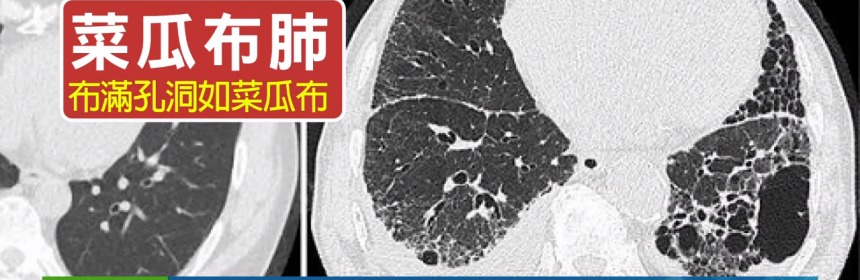

久咳不癒以為是感冒嗎? 小心可能是菜瓜布肺找上門

很多人都有久咳不會好的經歷,但大多都會認為只是一般的感冒就隨沒有選擇積極治療,但其實有一種嚴重的肺部疾病,其實也會有久咳不癒的病徵,它叫做特發性肺纖維化,俗稱菜瓜布肺,因為與感冒症狀雷同,經常會錯過黃金治療時機。